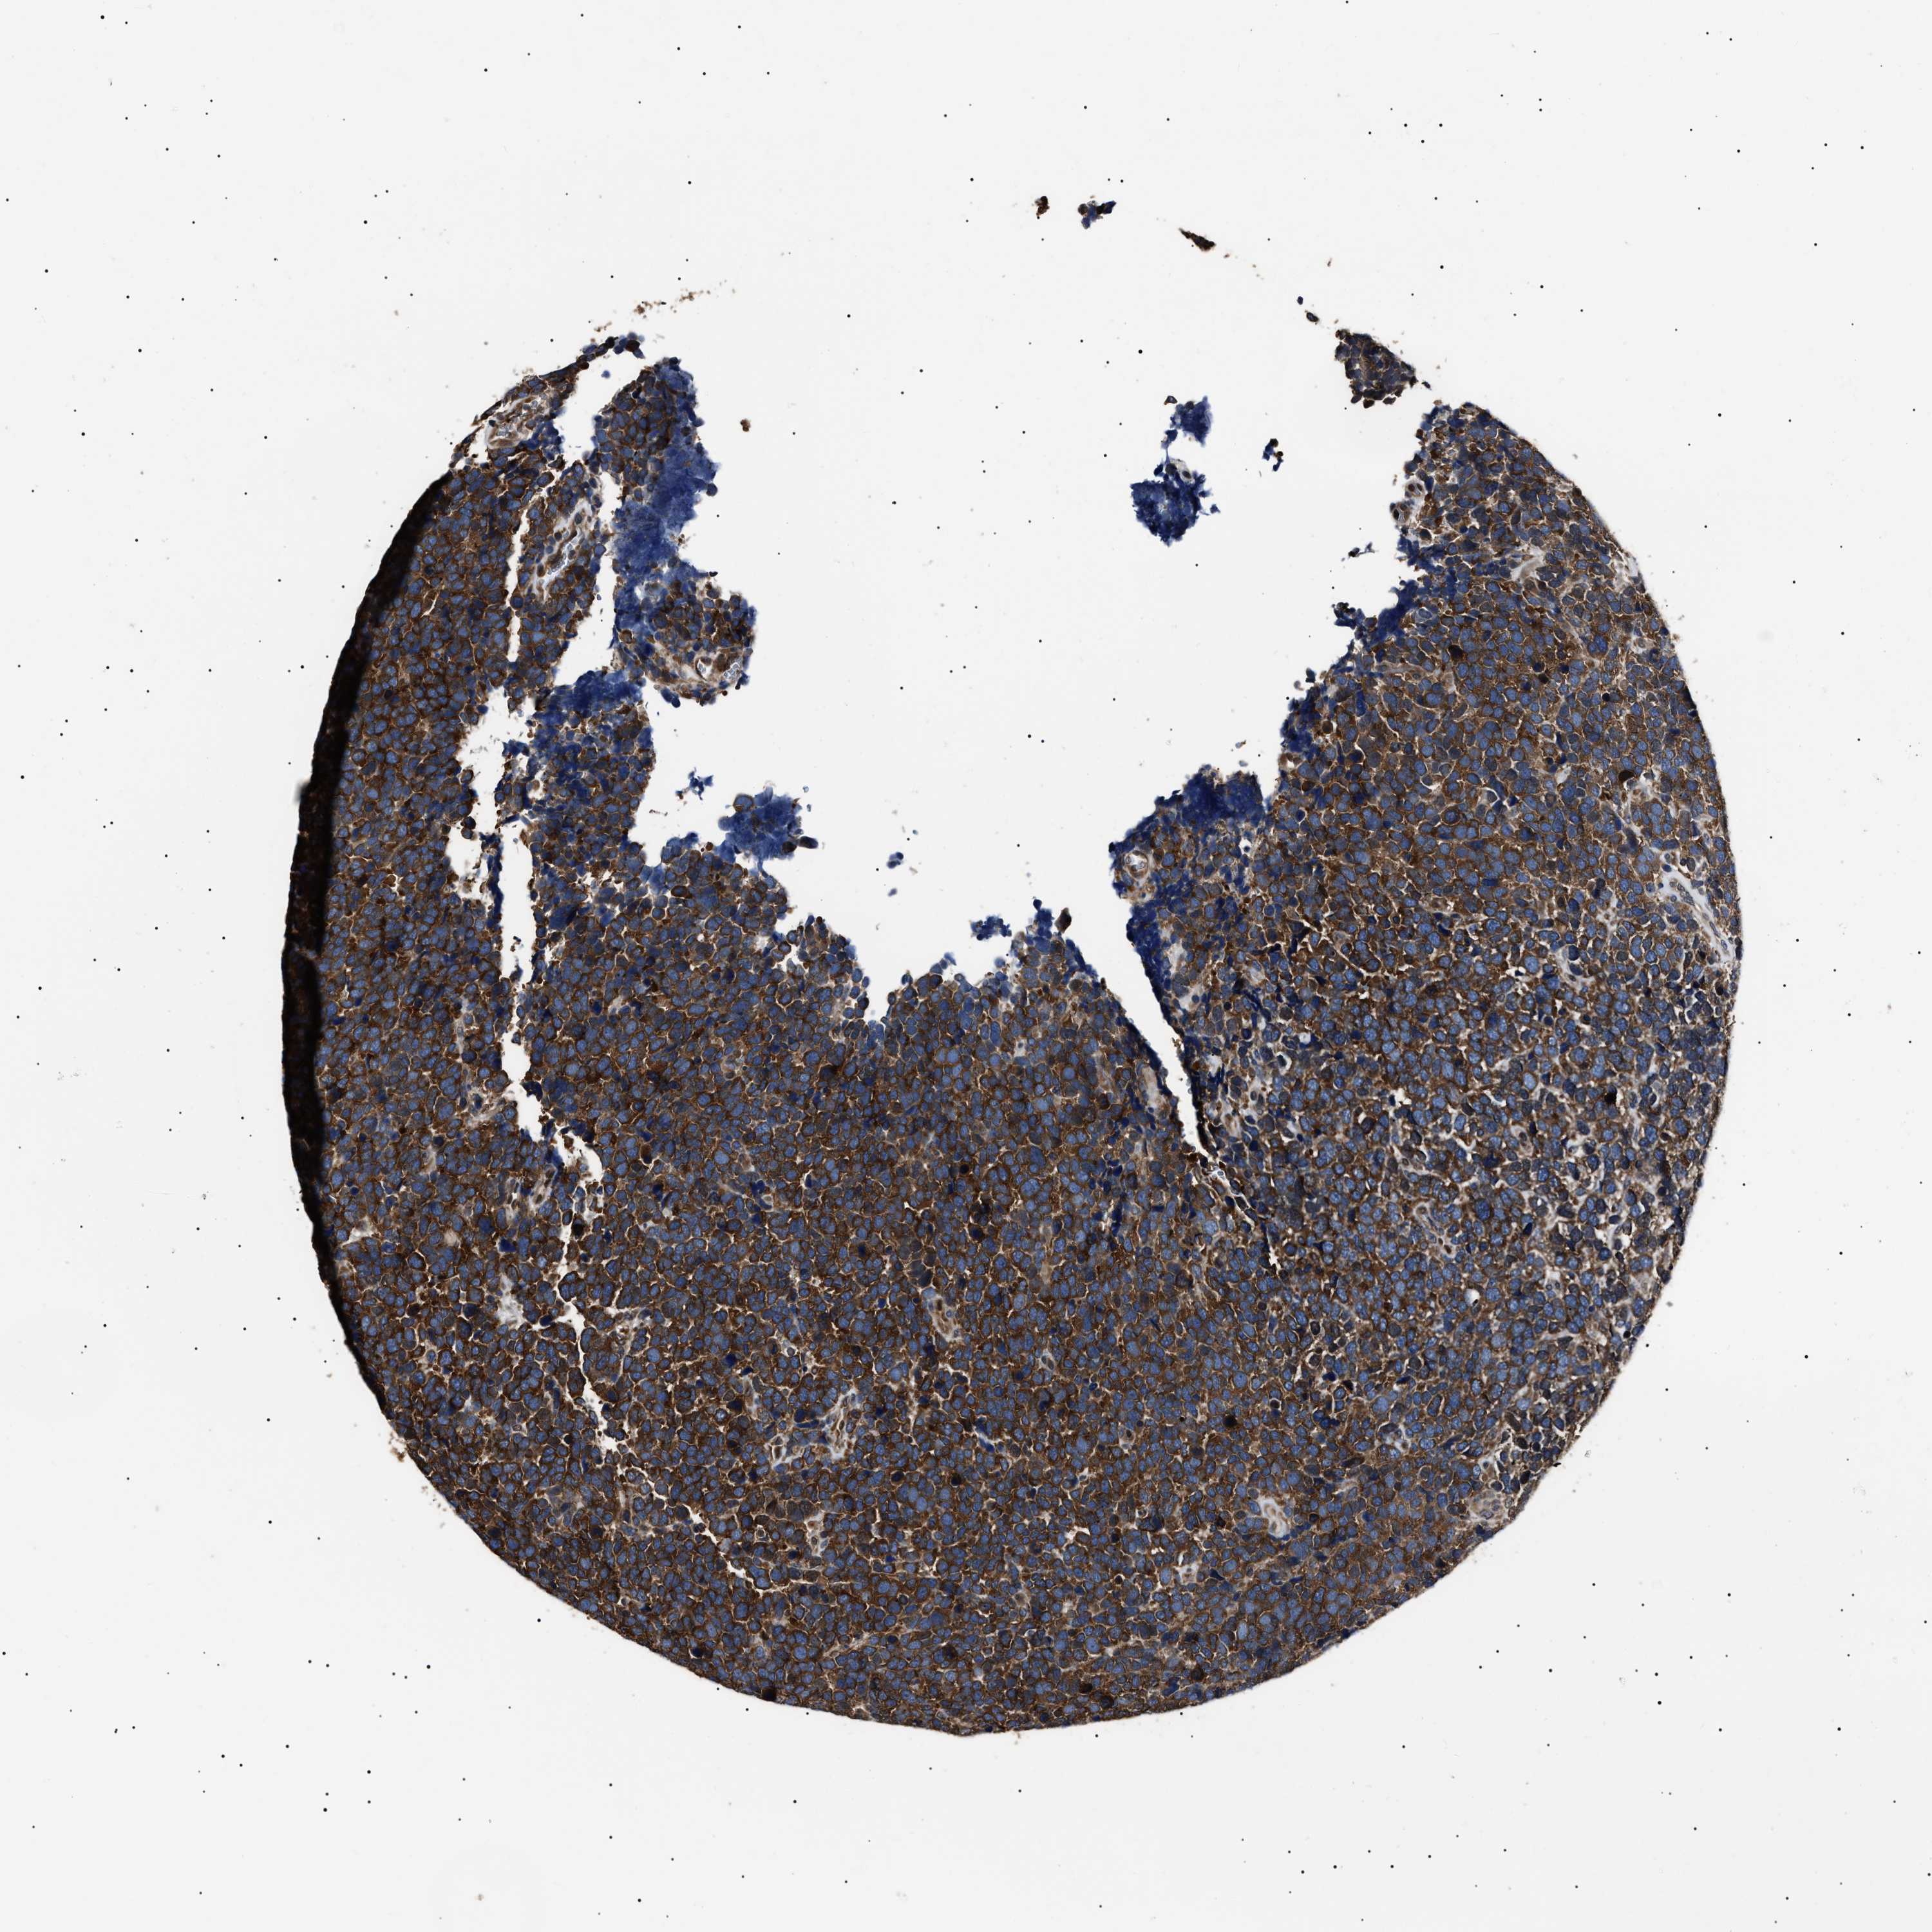

UROTHELIAL CANCER - Protein expressioni

A mouse-over function shows sample information and annotation data. Click on an image to view it in a full screen mode. Samples can be filtered based on level of antibody staining by selecting one or several of the following categories: high, medium, low and not detected. The assay and annotation is described here.

Note that samples used for immunohistochemistry by the Human Protein Atlas do not correspond to samples in the TCGA dataset.

Antibody stainingi

Antibody staining in the annotated cell types in the current human tissue is reported as not detected, low, medium, or high, based on conventional immunohistochemistry profiling in selected tissues. This score is based on the combination of the staining intensity and fraction of stained cells.

Each image is clickable and will lead to virtual microscopy that enables deeper exploration of all samples and also displays staining intensity scores, fraction scores and subcellular localization as well as patient and tissue information for each sample.

Antibody HPA018520

Antibody HPA021051

Antibody HPA029426

Urothelial carcinoma, Low grade

Urothelial carcinoma, High grade